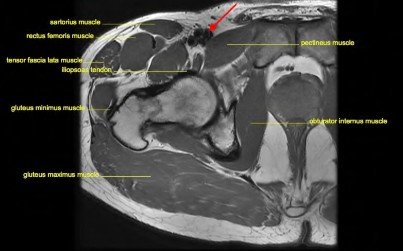

A 75-year-old man underwent total hip arthroplasty 10 years ago. He now reports mild groin pain which has been increasing lately. What is the most likely explanation for the finding in Figure A indicated with the arrows?

Osteolysis of the pelvis is a common complication associated with total hip arthroplasty. Osteolysis affects sockets with and without cement, and has been attributed to the biologic reaction to wear debris. With well-fixed cementless sockets, an expansile pattern of osteolysis is usually seen.

The radiographic appearance has a radiolucent area that starts at the implant-bone interface and expands into the cancellous bone away from the implant.

This pattern of osteolysis can be explained with the concept of effective joint space. This concept states that joint fluid and wear particles will flow according to pressure gradients and follow the path of least resistance.

The Level 5 review article by Chiang discusses osteolysis in further depth.